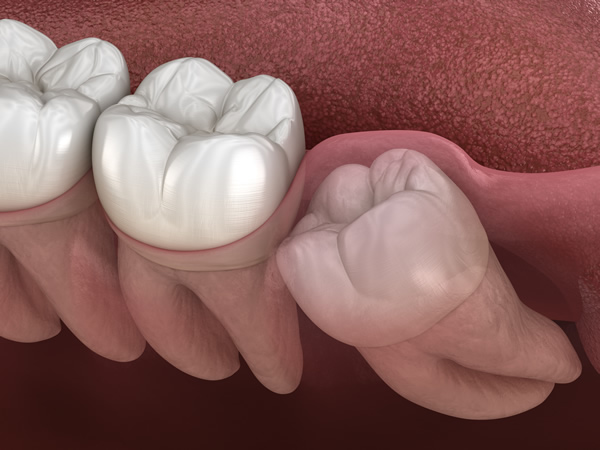

水平埋伏歯(横向きに生えた親知らず)

水平埋伏歯とは、横向きに生えている歯のことです。

この状態では、隣の歯を押してしまい、痛みや歯並びの乱れを引き起こすことがあります。また、汚れがたまりやすく、虫歯や歯周病の原因になるケースも少なくありません。骨や神経に近い位置にあることが多く、抜歯には高い技術が求められます。

当院では、精密な診断と高度な技術をもとに、こうした難しい抜歯にも対応しています。他院で抜歯が難しいと言われた場合でも、お気軽にご相談ください。